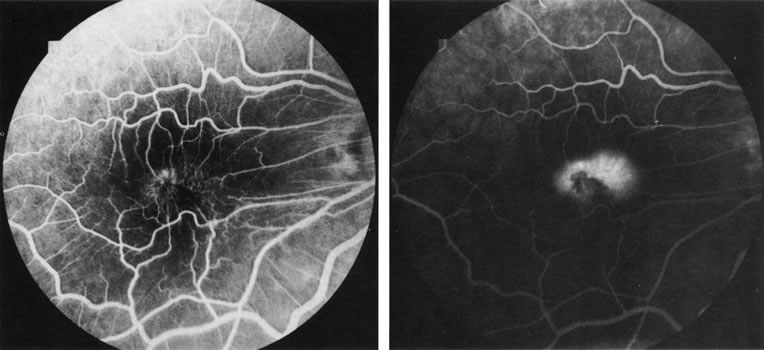

Fig. 3. Notched retinal pigment epithelium (RPE) detachment. There is a notch at the superotemporal border of a large RPE detachment that fills unevenly with fluorescein (large arrowhead). There is also a superior neovascular complex (small arrowhead) that hyperfluoresces. (Courtesy of Dr. Kenneth G. Noble.)

Fig. 4. Subretinal blood from a choroidal neovascular membrane. A small hemorrhage has layered out at the inferior aspect of a large retinal pigment epithelium (RPE) detachment. A shallow overlying neurosensory detachment can be appreciated as the slightly darkened, narrow band that surrounds the RPE detachment. The neurosensory detachment is being filled with fluorescein through a break in the RPE. The subretinal neovascular membrane, not clearly evident in this early-phase fluorescein angiogram, is at the nasal edge of the RPE detachment, near the optic disc.